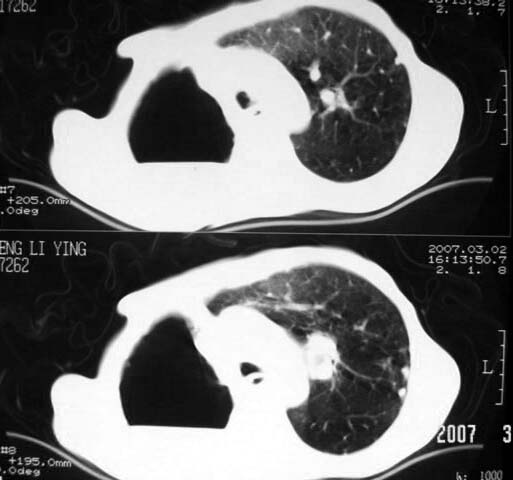

以下是引用dyqct在2007-3-2 22:04:00的发言:[br]考虑:1、右侧毁损肺伴支气管胸膜瘘(多条支气管与胸腔相通、液气胸);[br] 2、左肺浸润型肺结核。[br][br][br][br]